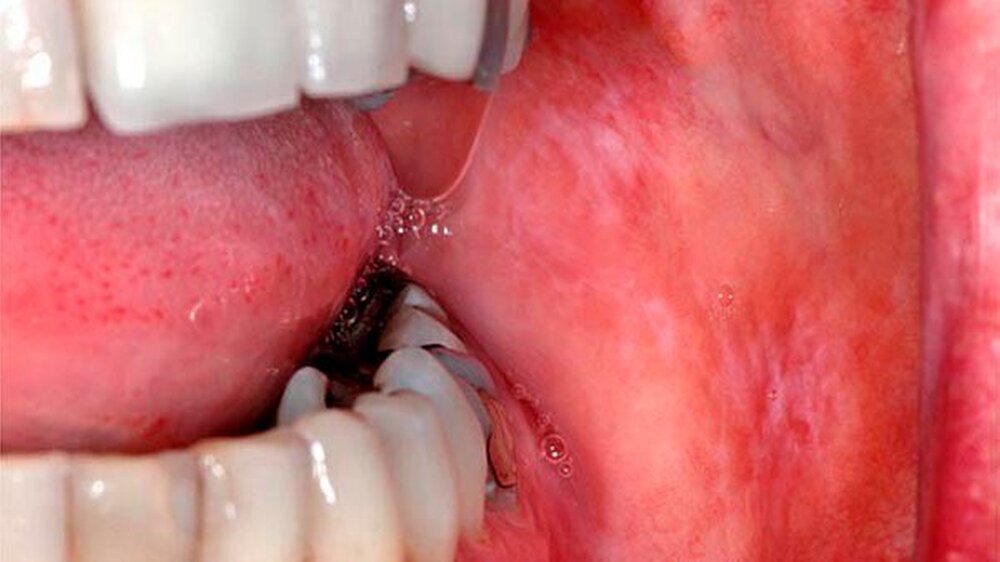

Eine 47-jährige Frau stellte sich Anfang 2012 in der Sektion für Klinische und Experimentelle Orale Medizin am Universitätsklinikum Leipzig wegen länger bestehenden typisch weißlichen Schleimhautveränderungen ohne subjektive Beschwerden vor. Nebenbefundlich bestand eine mit L-Thyroxin behandelte Hypothyreose. Beidseits im Planum buccale und in der Kieferwinkelregion rechts zeigten sich sogenannte Wickham-Streifungen mit stellenweise plaqueartigen Inseln sowie einer schwarzen Pigmentierung vestibulär von Zahn 47 (Abb. 1a, b).

Dieser Befund passte zu einer erosiv-entzündlichen Veränderung der Mukosa. In der Biopsie der Wangenregion rechts zeigte sich eine geringradig regeneratorische Epithelhyperplasie. Als Diagnosen wurden ein kombiniert retikulär-erosiver Lichen sowie eine lichenoide Kontaktläsion regio 47 und eine Einlagerung von exogenen Pigmenten («Amalgamtätowierung») in regio 47 beschrieben. Vor einem Austausch der Füllungen wurde der Patientin eine erneute Epikutantestung empfohlen. Hier fand sich eine polyvalente Sensibilisierung zusätzlich auf Epoxidharz, Amalgam (mit Zink) und Quecksilber (II)-amid-chlorid sowie vier der getesteten Proben (Tab. 1).